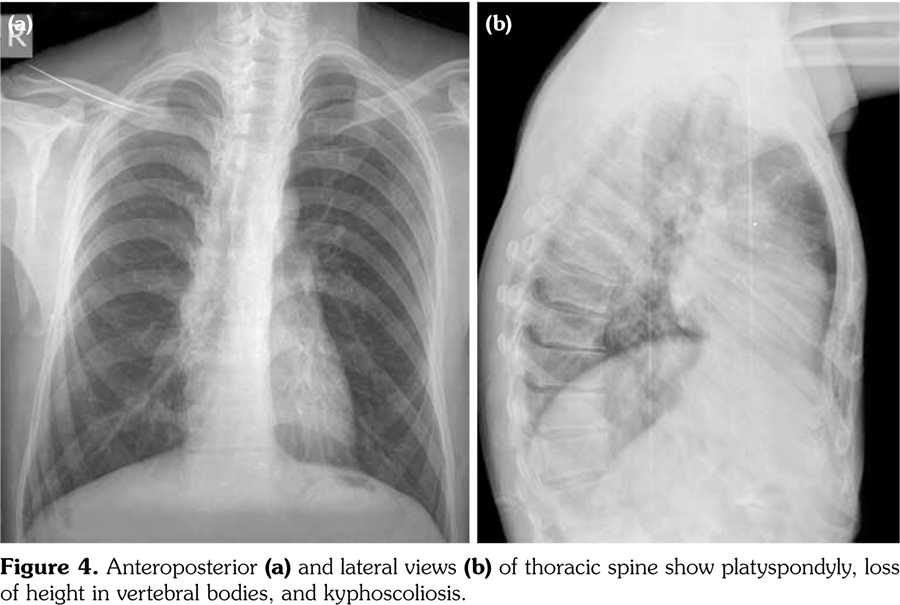

Radiographs of the hands showed enlargement of metaphyses, flattening of epiphyses, and narrowing of joint spaces with no erosions. Lateral radiograph of the foot revealed bilateral large ossified trigonum attached to the talus (mega os trigonum) (Figure 3). Radiographs of the spine showed increased kyphosis, generalized platyspondyly particularly at the thoracolumbar junction, and irregularity of the vertebral end- plates (Figure 4). Magnetic resonance imaging of thoracolumbar spine demonstrated irregularity in vertebral end-plates, multiple disk herniations, and platyspondyly (Figure 5). Dynamic contrast- enhanced magnetic resonance imaging of the wrist did not reveal any signs of synovial inflammation.

Clinical features of PPD have been described in several reports.(9-11) The radiographic features include varying degrees of epiphyseal involvement with enlargement of the epi-metaphyseal region, progressive joint narrowing, generalized platyspondyly, multiple intervertebral herniations, kyphoscoliosis, mega os trigonum and bone destruction with aging.(2,6,10) Our patient had progressive restriction of several joints, IP enlargements, dysplastic bone/cartilage changes, mega os trigonum and platyspondyly, with normal acute phase reactants. The presence of dysmorphic features and the absence of inflammatory signs should alert the physicians for the possible hereditary dysplasias like PPD.